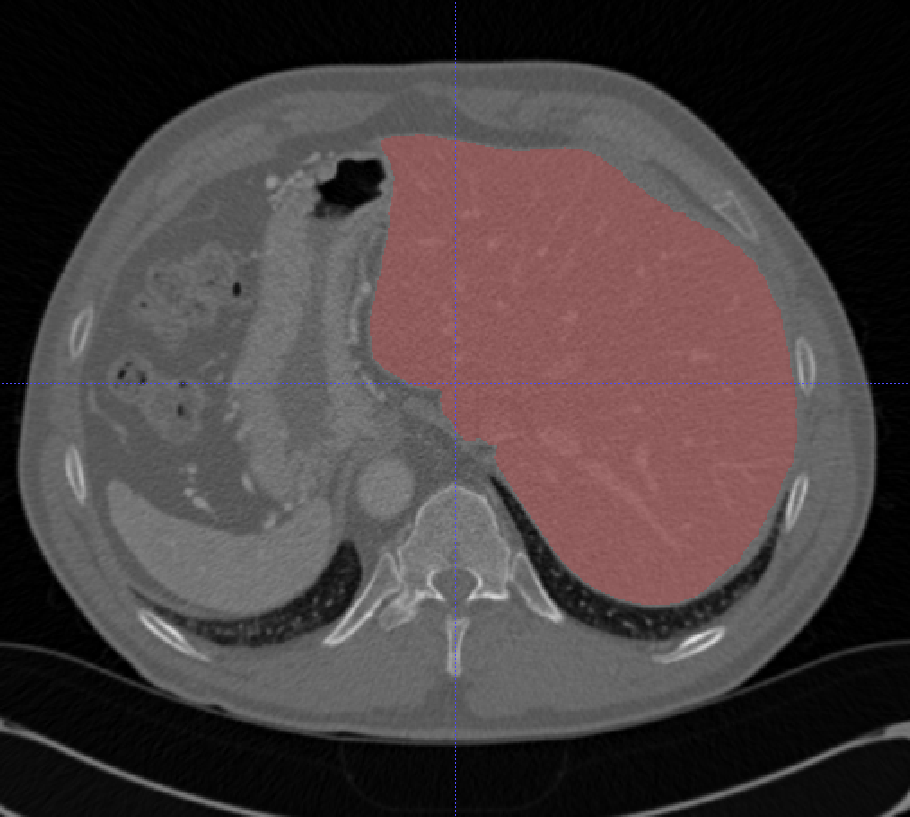

- 肝脏

| LiTS | 肝脏/肝脏肿瘤 | 分割 | CT | 131+70 | 0/1标签 | nii | CC BY-NC-ND 4.0 |

LiTS数据集包含131组训练扫描和70组测试扫描,其中70组测试数据标签不公开。LiTS训练集中包含3DIRCADB中的所有数据,所以不要合并这两个数据集。Medical Segmentation Decathlon中肝脏分割的数据集就是LiTS。

| Sliver07 | 肝脏 | 分割 | CT | 20+10 | 0/1标签 | MetaImage | Other |

这个数据集比较老了,现在用的也比较少,一些研究会将sliver和lits合起来,这样基本上就是所有常用的关于肝脏分割的公开数据了。mhd格式可以用 SimpleITK 读,在medseg项目中有转换成nii的脚本

| 3D-IRCADb 01 02 | 肝脏/肝肿瘤 | 分割 | CT | 20+2 | surface mesh | dcm | CC |

3D-IRCADb是比较早的一个数据集,有两个子集,分别包含20组和2组CT片子。

| CHAOS | 肝/肾/脾 | 分割 | CT+MRI | 40CT+120MRI | 0/1标签 | dcm | CC 4.0 |

CHAOS是一个多脏器,多模态分割数据集。